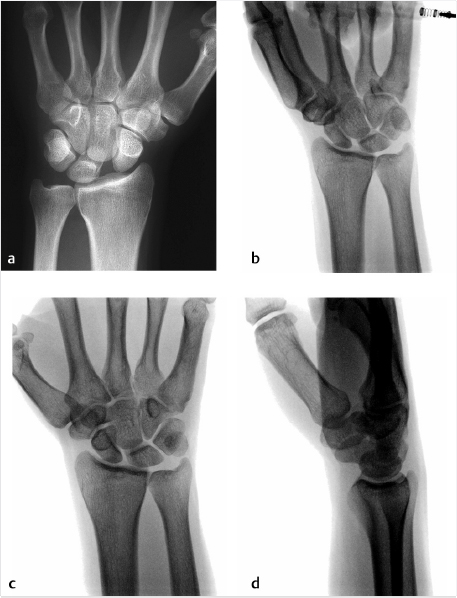

There are many radiographic indicators, including diastasis between the scaphoid and lunate on the PA radiograph greater than 3 mm (► Fig. 66.2a). Moreover, a clenched fist/pencil grip view (► Fig. 66.2b) drives open the SL interval and can accentuate the deformity. A cortical ring sign (► Fig. 66.2c) and an increased scapholunate angle (► Fig. 66.2d) are other indicators of this pathology. MRI studies are often performed (► Fig. 66.3), but have variable rates of sensitivity and specificity. 3 The gold standard for diagnosis of a SL ligament rupture remains diagnostic arthroscopy. The Geissler classification is used to characterize a tear. 4